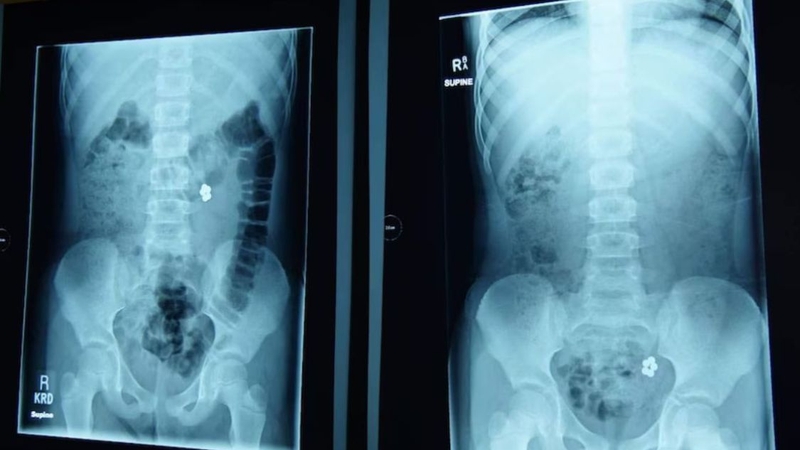

Trẻ nuốt phải viên bi có sao không? Tình huống này không phải lúc nào cũng gây nguy hiểm nghiêm trọng. Tuy nhiên, cha mẹ nên theo dõi sát sao các dấu hiệu bất thường để phát hiện kịp thời những biến chứng có thể xảy ra. Khi nghi ngờ trẻ nuốt phải viên bi, tốt nhất hãy đưa trẻ đến cơ sở y tế để chụp X-quang, nội soi và được các bác sĩ hỗ trợ xử lý kịp thời.